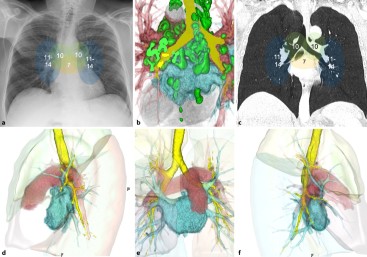

Computertomografie | Moderne Bildgebung des Lungenhilus | springermedizin.de